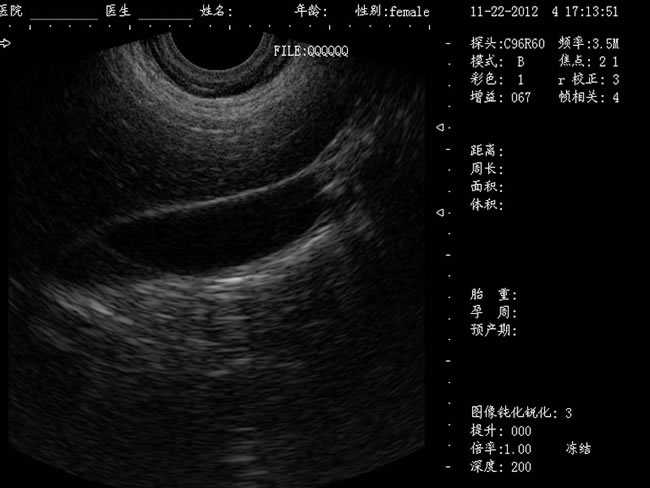

DW-460

功能特點:

婦產科手術監視儀-可視人流機掃描角度:

a) 6.5MHz腔內探頭:152º可視可調;

b) 3.5MHz凸陣探頭:60º可視可調;

TGC 調節:總增益、8 段TGC 調節器。

圖像放大:實時放大(16 級可調),局部放大(≥2 倍)。

圖像調節:黑白、左右、上下、亮度、對比度、焦點數、焦點間距、焦點位置、動態范圍、掃描角度、掃描線密度、聲功率、幀相關、M 速度。

圖像處理:圖像平滑/銳化、組織諧波、伽瑪校正、直方圖。

注釋功能:日期,時鐘,姓名,病歷號,性別,年齡,醫生、醫院、全屏幕字符編輯。

體位標記:≥30 種。